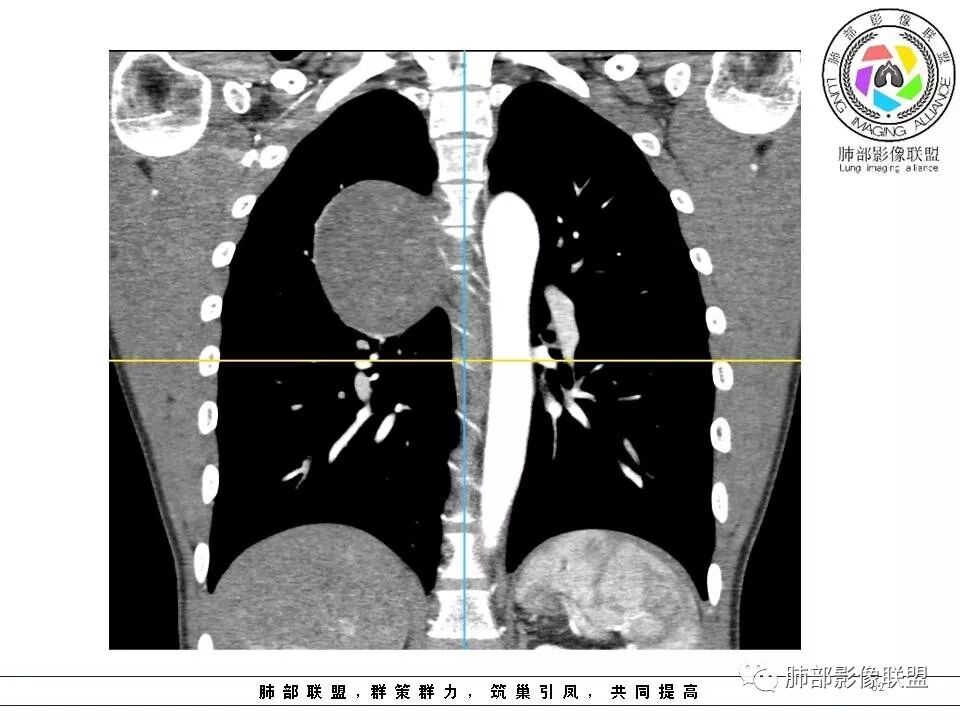

右后纵膈脊柱旁软组织占位,形态规则类圆,边缘光整,肺组织受压,胸膜尾,肋间动脉供血。中度不均匀延迟强化。

后纵隔脊柱旁占位性病变,疾病谱有神经鞘瘤,sft,节细胞瘤,髓外造血。此例有胸膜尾征,蛇纹征 ,延迟强化。考虑胸膜孤立性纤维瘤。看到有供血动脉,但不知道是哪里的血管。

后纵隔类圆形新生物,边缘光滑,胸膜尾征明显,贴近脊柱,蛇纹,血供丰富,考虑后纵隔软组织肿瘤,具体类型看不出来,鉴别神经鞘瘤。

右后纵膈脊柱旁软组织占位,边界清晰,光整,肺组织受压。胸膜被掀起,肋间动脉供血,中度不均匀延迟强化。考虑神经鞘瘤,不除外纤维瘤

右后纵膈脊柱旁软组织影,与纵隔结构分界不清,形态规则类圆,边缘光整,肺组织受压,胸膜尾,肋间动脉供血。肺动脉推移,中度不均匀延迟强化。考虑神经来源,神经鞘瘤,神经纤维瘤二者不易鉴别。

青年男性,间断胸痛;右侧脊柱旁可见一类圆形软组织密度影,密度欠均匀,增强扫描呈轻中度持续强化,邻近肺组织及肺动脉推移,可见肋间动脉供血,部分胸膜下脂肪可见,部分层面似见与右侧椎间孔相连。考虑后纵隔神经源性肿瘤。

后纵隔脊柱旁占位性病变,有胸膜尾征,胸膜下脂肪可见,蛇纹征,明显强化。考虑孤立性纤维瘤。

1.右上胸内脊柱旁类圆形肿块,质地似乎比较坚实,密度稍显不均,但未显示明确的坏死。

如此密度形态的病灶位于肺边缘首先应当想到孤立性纤维瘤,可相邻胸膜未见明显的异常强化和胸膜方向延伸。

2.肋间动脉病供血也提示肿块来自后纵隔?